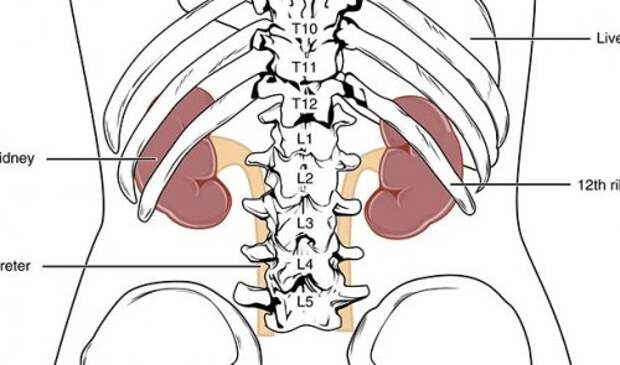

3. У них есть излишние органы.